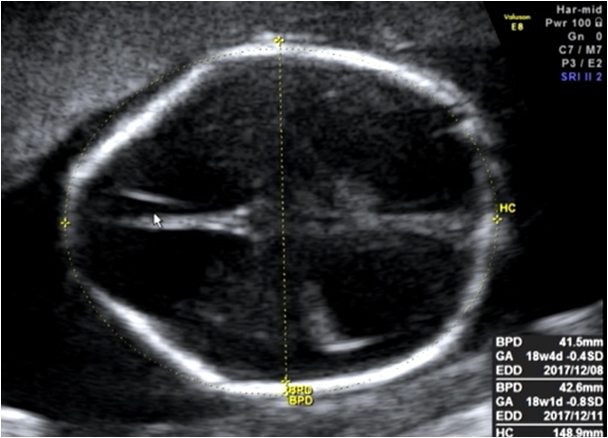

レモンサインは、赤ちゃんの頭の前方がほっそりとして、まるで頭のかたちがレモンに見えることから、その名前がつけられました。

お腹の中の赤ちゃんに、レモンサインとバナナサインがないかを確かめて、もしも疑われた場合には、しっかりと出生前診断のできる施設で再確認する。そのような体制を全国で構築します。